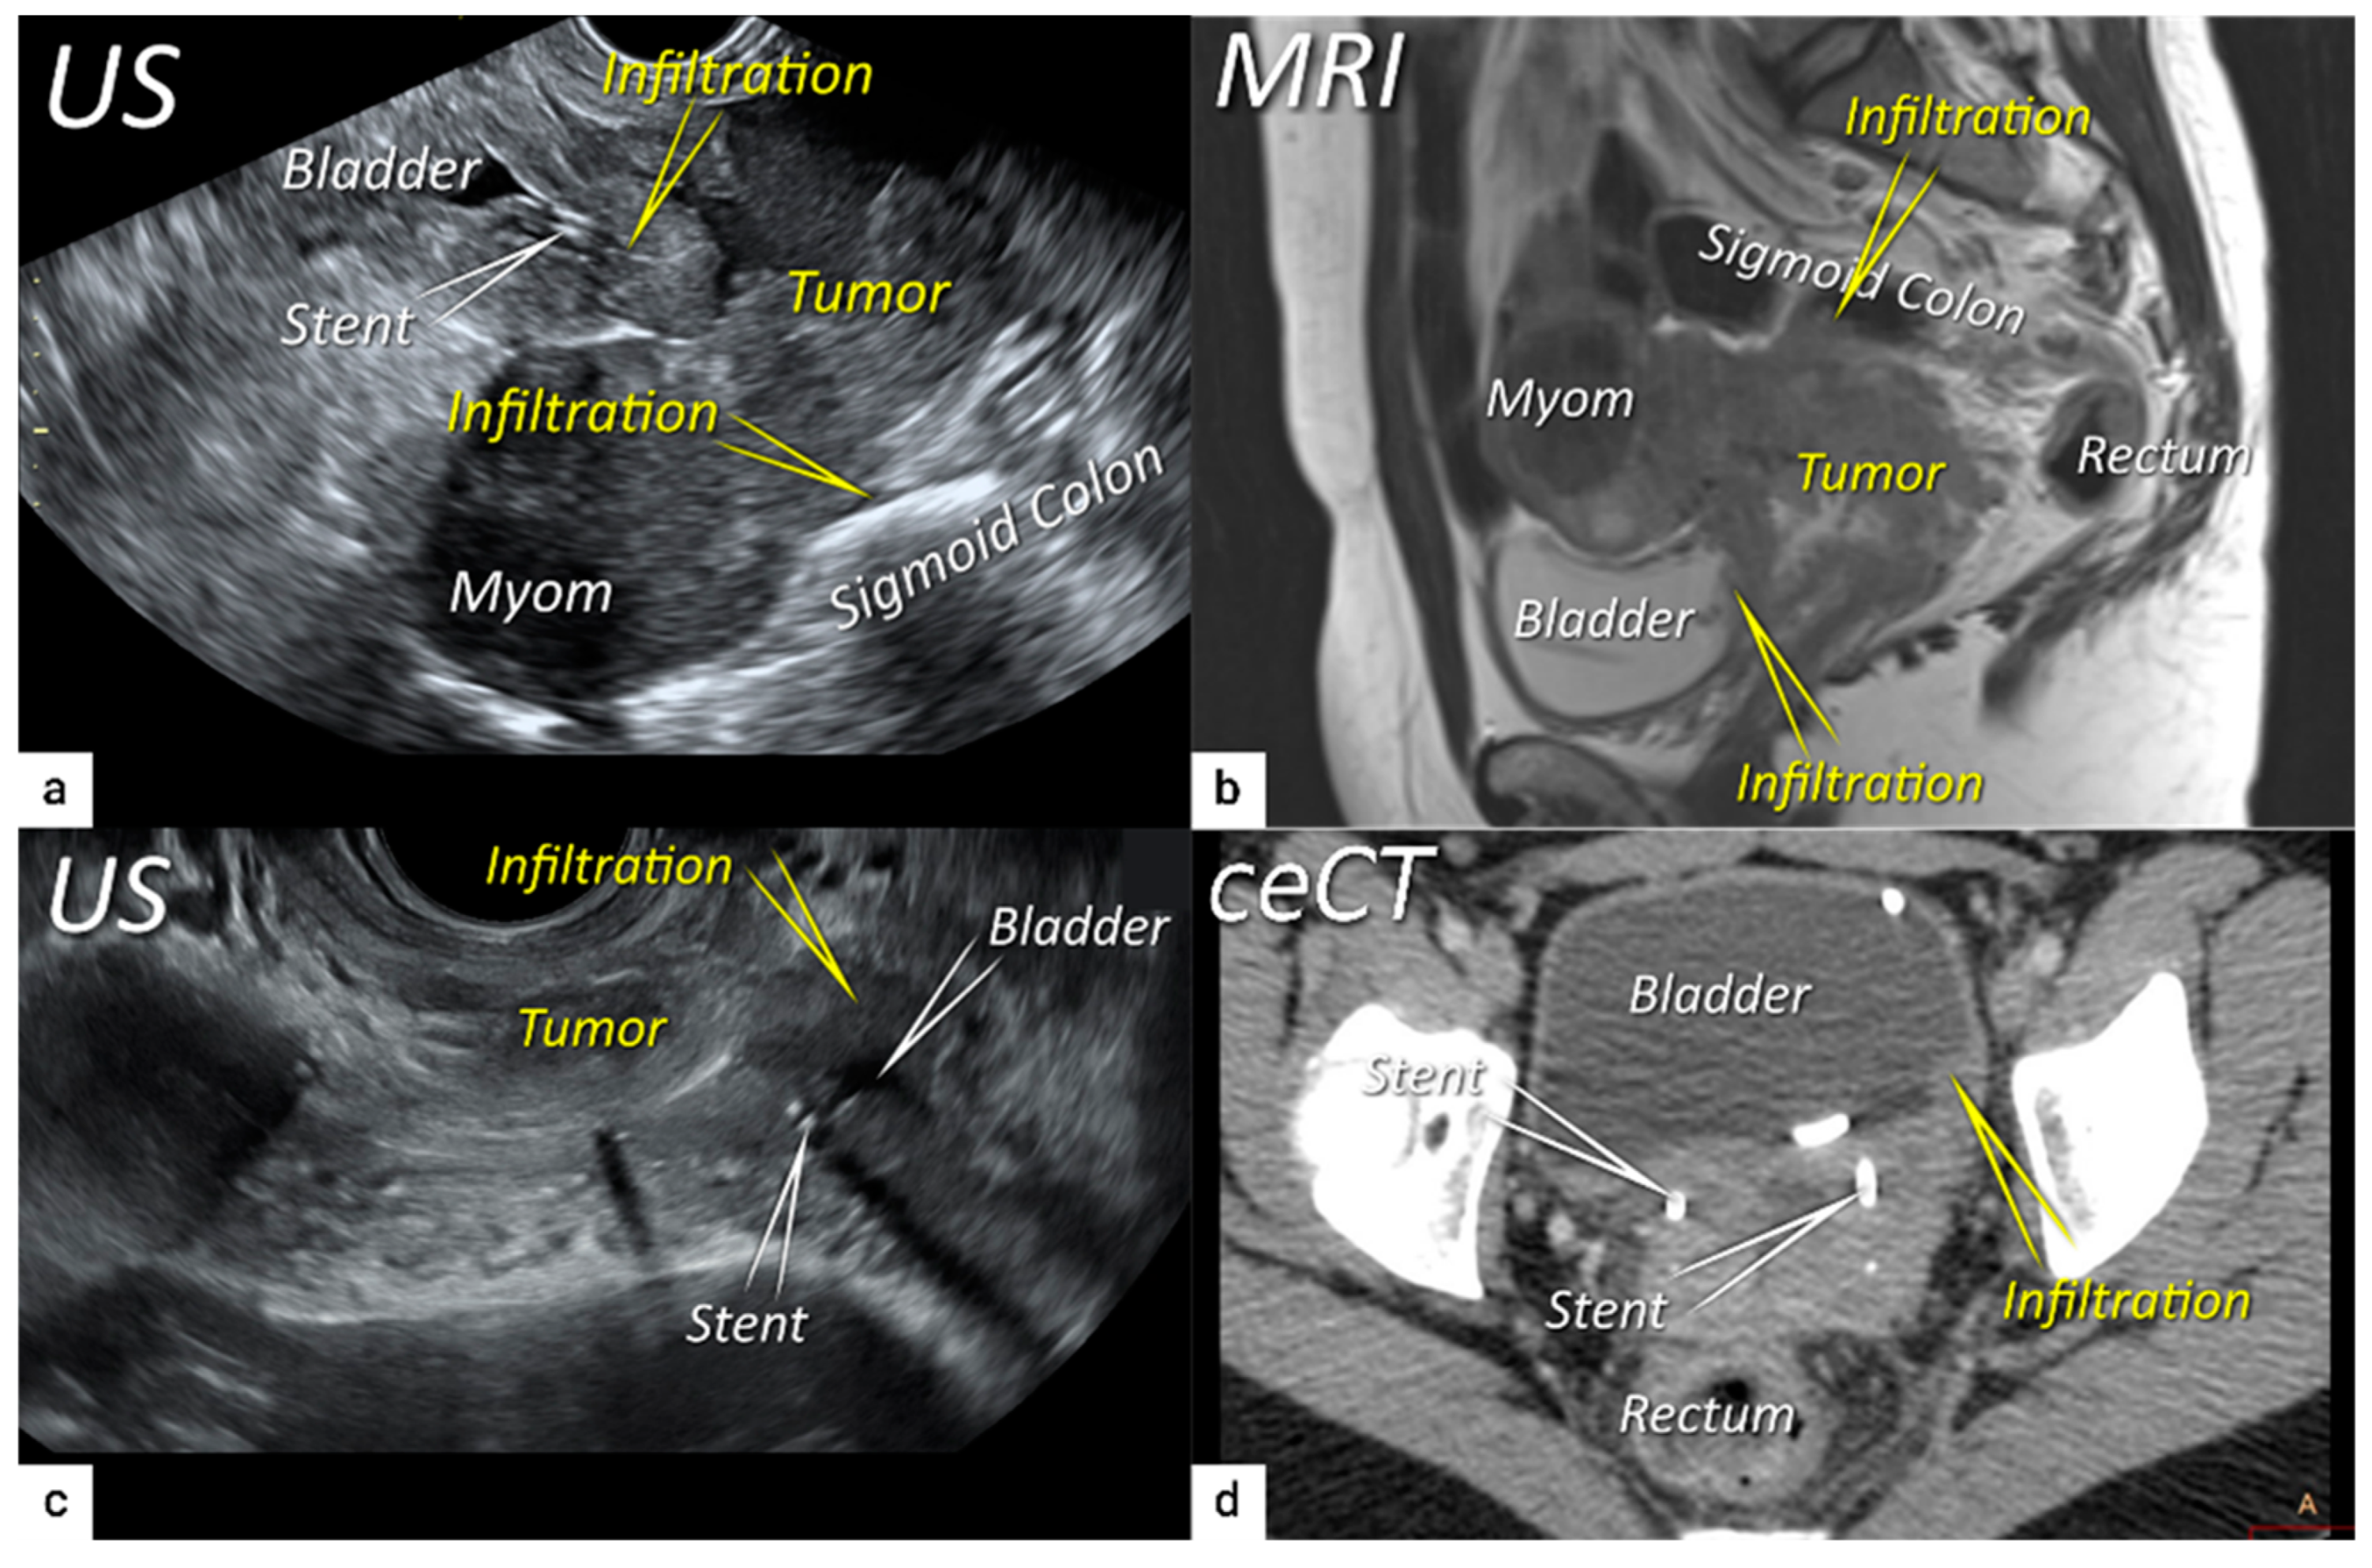

| T4 f | IVA f | Tumour invasion into the mucosa of the bladder or rectum (biopsy-proven) or into adjacent organs. | Tumour invasion into the mucosa of the bladder or rectum on imaging, confirmed by biopsy. US: Negative sliding sign, hypoechogenic tumour infiltration of bladder/rectal wall up to echogenic mucosa with polypoid tumour seen intraluminally. MRI: Focal or diffuse disruption of the normal T2-low signal intensity wall of the bladder/rectum, irregular or nodular wall, sometimes including an intraluminal tumour mass. Bulous edema sign, which is hyperintense thickening of the bladder mucosa on T2W images, is only an indirect sign of invasion and should not be regarded as T4 unless confirmed mucosal infiltration at cystoscopy. Infiltration of the posterior bladder wall without mucosal infiltration should not be regarded as T4a. |